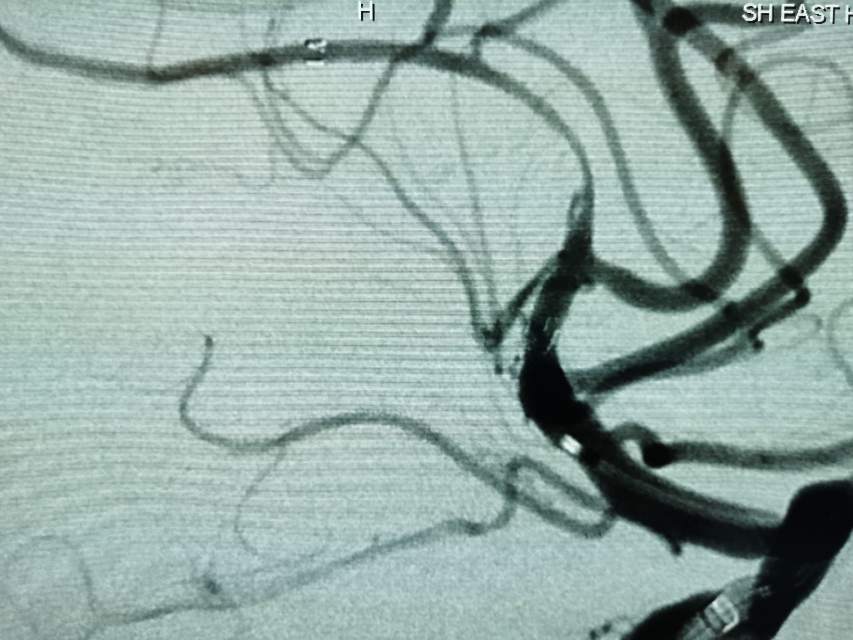

河南信阳帅哥,一个半月前突然出现左侧肢体肌力乏力、认知功能大幅下降、反应迟钝,在当地多家医院按照“脑梗塞”诊治后,症状未能缓解,仍呈进行性加重。经推荐转至我院寻求治疗,术前谈话之后,疫情期间,家里有急事需要处理,唯一的陪人回家了……。今日为患者手术,术中发现右侧大脑中动脉的一个分支出现多节段、长节段的夹层,血流仅剩断断续续的一条线,在血中飘摇,随时存在血管完全闭塞,脑梗塞继续加重,重者可能危及患者生命……,术中正确辨别真腔(误判后果严重),顺利打通重建血管,血流恢复……,手术只是整个治疗过程的一小部分,围手术期仍需要再接再励,帮助患者渡过风险期~~~

最后答案:血管夹层是导致青壮年自发性脑梗塞的罪魁祸首